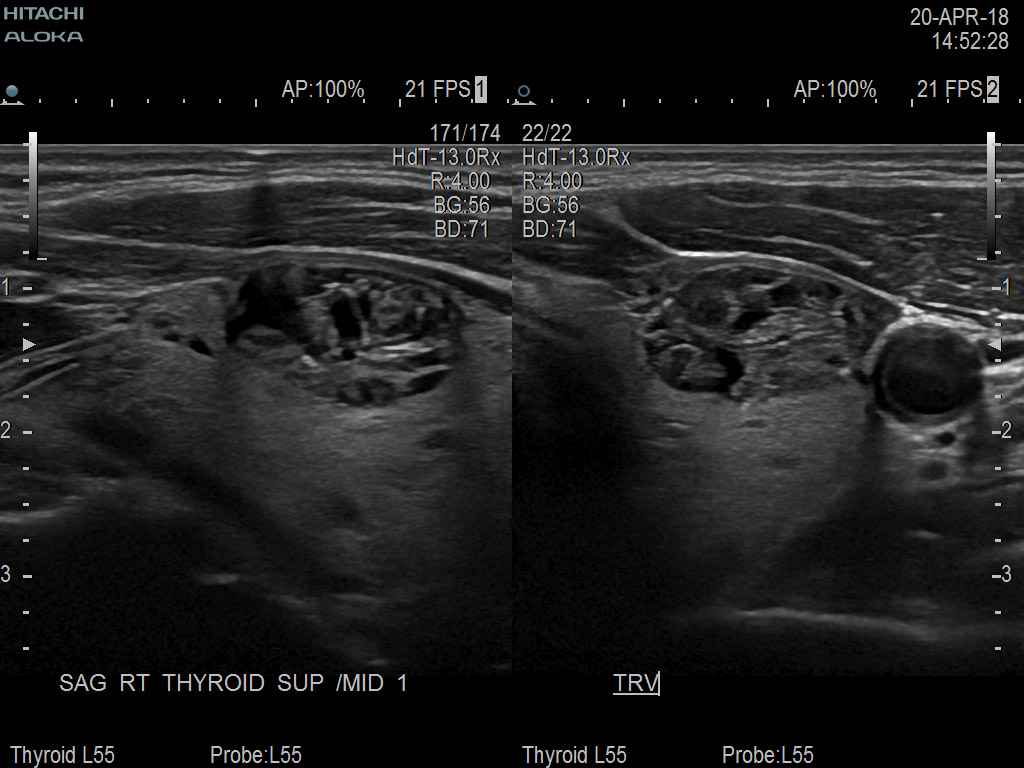

Superior guidance for all applications

Fujifilm Healthcare Americas is committed to designing tools that help surgeons navigate inside the human body and provide the necessary information to immediately make critical surgical decisions.

Fujifilm Healthcare's dedication to Surgeons provides outstanding ultrasound technology, professional support and the specialized tools necessary to best perform comprehensive real-time ultrasound imaging in Breast Surgery, General Surgery, Laparoscopic Surgery, Neurosurgery, Robotic Surgery and Surgical Oncology.

Arietta 70

Recognized for our outstanding image quality, outstanding system reliability and intuitive use of cutting edge technology, Fujifilm Healthcare remains the standard in the field of Surgery.

The Arietta 65 has many advanced and unique probes that fully cover the expanding range of procedures that benefit from ultrasound guidance.

Recognized for our outstanding image quality, outstanding system reliability and intuitive use of cutting edge technology, Fujifilm Healthcare remains the standard in the field of Surgery.

Imaging Clearly Defined

State-of-the-art digital architecture and advanced imaging features to redefine the capabilities of surgical ultrasound.